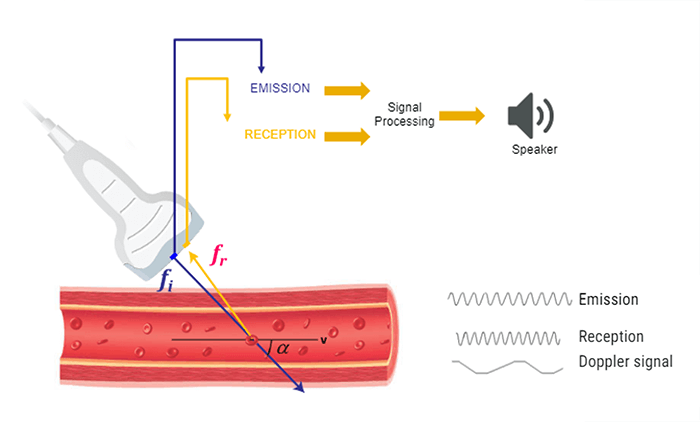

The same transducer acts as a transmitter and receiver in Doppler ultrasound applications. When using Doppler ultrasound technique to examine the blood flow in a vessel, the returning backscattered echoes from blood are detected by the transducer. These returning signals (Fr) are then processed to detect any frequency shifts by comparing these signals to the transmitted Doppler signals (Ft). The frequency shift detected will depend on two factors: the magnitude and the direction of the blood flow.

Doppler Equation

Let’s consider an example of a simple blood vessel. As shown in this figure, the transducer will first transmit a signal with frequency Ft, then this transmitted signal will reach a blood vessel. The transducer will receive the backscattered signals coming from the red blood cells at a frequency Fr.

The Doppler frequency shift (δf) is calculated by subtracting the transmitted signal Ft from the received signal Fr. As mentioned previously, this effect is used to study blood flow by measuring the frequency shift of echoes scattered by moving red blood cells.

The Doppler equation shows the relationship between the transmitted Doppler shifted signal (Ft) and the blood flow velocity (V): V = c/(2ft cos a).δf, where the following represent: δf is the Doppler-shifted signal, Ft is the transmitted Doppler frequency, c is the propagation speed of ultrasound in soft tissue, V is the velocity of the moving blood, and a is the angle between the Doppler ultrasound beam and the direction of blood flow.

The number 2 is a constant indicating that the Doppler beam must travel to the moving target and then back to the transducer.

Effect of Angle

Note that the Doppler frequency also varies according to the angle alpha. The value of cosα varies with the angle from 0 to 1. When α = 0°, cosα = 1 and when α = 90°, cosα = 0.

For a constant flow velocity (V), the maximum value of cosα and therefore the highest value of the Doppler-shifted signal (δf) is at an angle of 0°. This corresponds to a Doppler beam which is parallel with the vessel, which can rarely be achieved in practice.

Theoretically, when α = 90° this means the blood flow is perpendicular to the Doppler beam, cosα = 0 and no Doppler-shifted signals will register.

In practice, when measuring the blood flow, a Doppler beam angle between 30 and 60° ensures reliable Doppler-shifted signals. Avoid using angles greater than 60 degrees and remember no Doppler-shifted signals are generated at 90 degrees. The smaller the angle, the more reliable is the recorded Doppler speed.

Doppler Signal

Ultrasound machines transmit high-frequency waves between 2 and 20 MHz. Measuring the blood flow velocities using the Doppler technique gives Doppler-shifted signals which lie within the audible range. Therefore, all Doppler systems have audio outputs and are very useful during a Doppler examination.

The Doppler frequencies will be processed and it will be possible to analyze the blood flow velocities by simply hearing the Doppler signal through loudspeakers. Hearing the Doppler signal also allows the sonographer to easily distinguish between laminar and turbulent flows. Please note that laminar flows produce a uniform sound, while turbulent flows, emit a sharp sound.